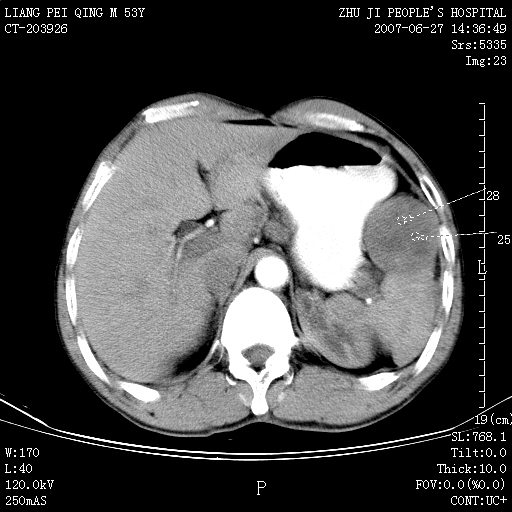

以下是引用余辉在2007-6-27 18:46:00的发言:[br]病灶多发,内可见大片状低密度区,病灶病灶等密度区轻度强化,动脉期后期病灶低密度区与高密度区对度增加,考虑1淋巴瘤2转移瘤3血管内皮细胞瘤(不知有否静脉期及延迟期扫描)

以下是引用zzzzhhhhaaaannnn在2007-6-27 20:44:00的发言:[br]脾脏 肋骨转移可能性大,下腔静脉内有癌栓

以下是引用狙击手在2007-6-28 10:35:00的发言:[br]1:定位:来源于脾脏。2:强化:强化,但不均匀。3:下腔静脉癌栓?下腔静脉充填不均匀与增强时间有关,延时即可明确。4:肋骨破坏?看起来并不确切。综上考虑几个最常见诊断:1;淋巴管瘤;2;血管内皮肉瘤(高度恶性,早期即可转移,常见肝,肺,骨)3;转移瘤(无特征性,只有肝或其它腹腔脏器有类似病变时,才可提示之)